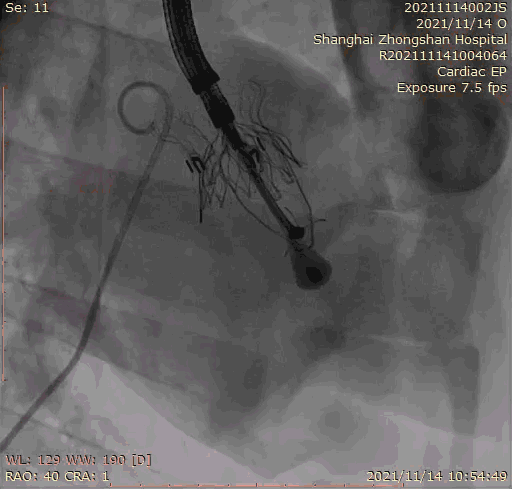

本次臨床前研究經(jīng)右側(cè)頸靜脈置入LuX-Valve Plus輸送系統(tǒng)可調(diào)彎鞘管,在DSA及超聲引導(dǎo)下將人工三尖瓣瓣膜植入到原有三尖瓣位置,利用獨特的錨定技術(shù)將人工瓣膜支架可靠固定在預(yù)定的位置。

Lux-Valve是全球第一款具有我國完全自主知識產(chǎn)權(quán)的經(jīng)導(dǎo)管介入三尖瓣置換系統(tǒng),利用前瓣夾持及室間隔錨定的復(fù)合方式進行瓣膜裝置的固定,不依賴瓣環(huán)徑向支撐力,同時采用自適應(yīng)復(fù)合裙邊材料,有效的貼合密封柔軟的三尖瓣瓣環(huán),針對于三尖瓣返流的患者有優(yōu)異的療效。Lux-Valve Plus采用全新的經(jīng)血管輸送系統(tǒng),經(jīng)頸靜脈入路創(chuàng)傷更小,可以進一步降低手術(shù)風(fēng)險。相信在后期正式臨床研究開展中,Lux-Valve Plus必定會為更多的三尖瓣反流患者帶來福音。